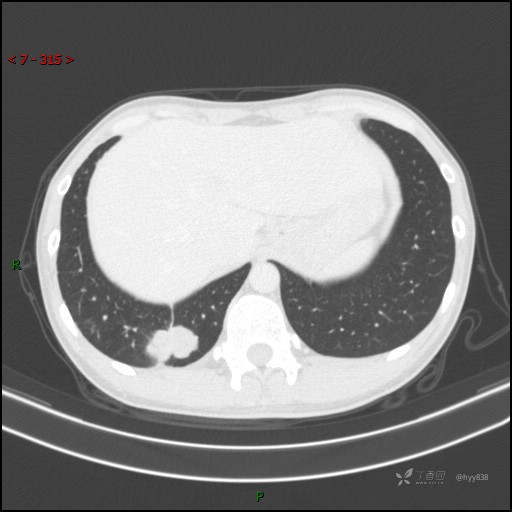

胸部CT平扫